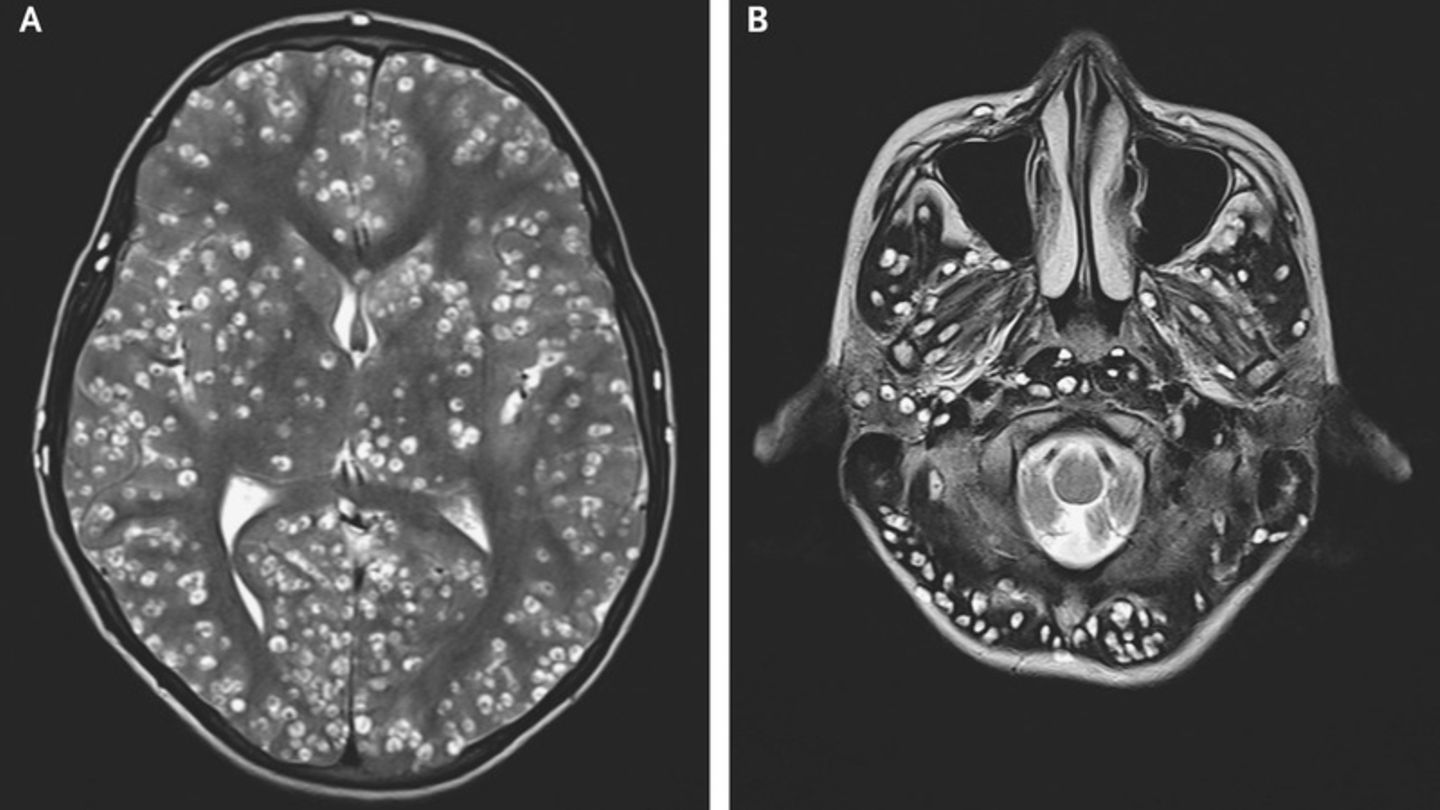

MRT zeigt Hirnschäden nach Infektion mit Bandwurm

Bei einem MRT seines Kopfes entdeckten die Mediziner Schäden in der Großhirnrinde und weiteren Teilen des Gehirns. Diese waren auf Zysten zurückzuführen, die sich als Folge einer Bandwurminfektion gebildet hatten - sprich: Die Larven des Parasiten hatten sich im Hirn eingelagert. Bei Ultraschalluntersuchungen des rechten Auges und Hodens wurden weitere Zysten entdeckt.